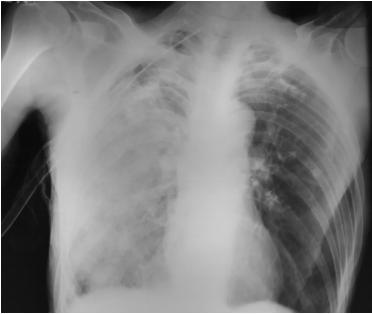

病人继续使用高流量氧气。两小时后,病人出现严重的胸部不适、咳嗽和呼吸急促。临床上有心动过速(脉率110/min)和低血压(血压64/46mmHg),血氧饱和度降至68%。胸部检查显示胸部右侧有粗糙的纹理。心电图及心肌酶测定排除了急性肺栓塞。行急诊床边便携式胸片正位片,显示右侧肺淤血和右侧ICD部位浑浊(图3)。根据上述检查结果,诊断为REPE。患者接受静脉输液和无创通气(NIV)支持。

图3 胸片显示右半胸非均匀性混浊